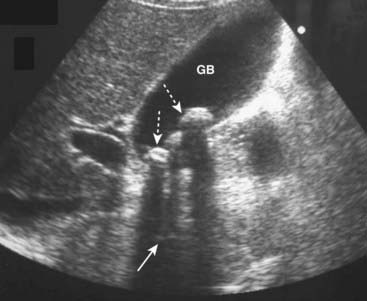

Figure 19-2 Cholelithiasis, sagittal view.

There are numerous echogenic stones (dotted white arrows) in the gallbladder (GB). The stones cast acoustical shadows as they reflect most of the sound waves (solid white arrows).

imageAcoustical shadowing describes a band of reduced echoes behind an echo-dense object (e.g., a gallstone) that reflects most, but not all, of the sound waves. While acoustical shadowing reduces the diagnostic effectiveness of ultrasound through such tissues as bone and bowel gas, its presence can have diagnostic value in identifying the presence of calculi, such as in the gallbladder and kidney (Fig. 19-3).

Figure 19-3 Acoustical shadowing.

There is a band of reduced echoes (solid white arrow) behind echogenic gallstones (dotted white arrows) that reflect most, but not all, of the sound waves. The presence of acoustical shadowing can have diagnostic value in identifying the presence of calculi in the gallbladder (GB).